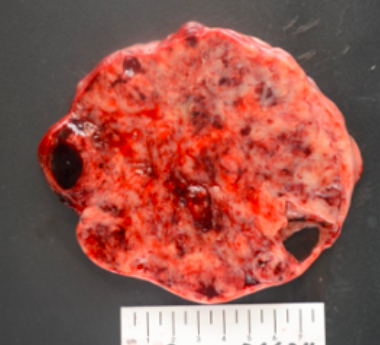

18 year-old female with 2 weeks of pelvic pain. CT showed a heterogeneous pelvic mass measuring 12.8 x 11.1 cm.CA-125 was 129 and AFP and beta-hCG (UPT negative) were not measured. She underwent right salpingo-oophorectomy. The ovary/mass measures 16.5 x 12 x 9.6 cm. Serially sectioning reveals a solid and partially cystic (90% solid, 10% cystic), variegated, homogenous, soft mass with punctate areas of hemorrhage. The fallopian tube grossly was not involved. Right external iliac and periaortic lymph nodes were involved by tumor. See below for the gross and microscopic photos of the ovary. The tumor cells show focal immunoreactivity for Pankeratin cocktail, AE1, AE3, Cam5.2 and 34BE12, patchy dot-like positivity with EMA, patchy and strong immunoreactivity for WT1 and SALL4, patchy immunoreactivity for Synaptophysin, focal positivity for Calretinin and CD10. Chromogranin and CD56, PAX8, OCT3/4, CD30, Inhibin, SF1, CD45, Desmin, GFAP and Sox10 were all negative in the tumor cells. INI1 expression was retained. What is the diagnosis?

This tumor is rare, occurs almost exclusively in women of reproductive age and children (median: 25 years). Tumors are usually large, solid, fleshy and tan to white to grey, often with hemorrhage, necrosis and cystic degeneration.